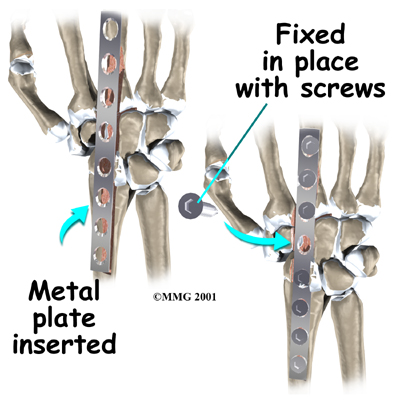

Many operations are used to treat problems in the wrist. A fusion surgery can get rid of pain and restore strength in badly degenerated wrist joints.

Many operations are used to treat problems in the wrist. A fusion surgery can get rid of pain and restore strength in badly degenerated wrist joints.

Fusion surgeries make the wrist strong again, but they greatly reduce the wrist's range of motion. This makes fusion surgery a poor choice for some people.

Related Document: A Patient's Guide to Wrist Fusion

If both wrists require surgery, many surgeons recommend fusing one wrist for strength and replacing the other wrist with an artificial wrist joint. This allows the patient to have one strong hand and one hand with a good range of motion.